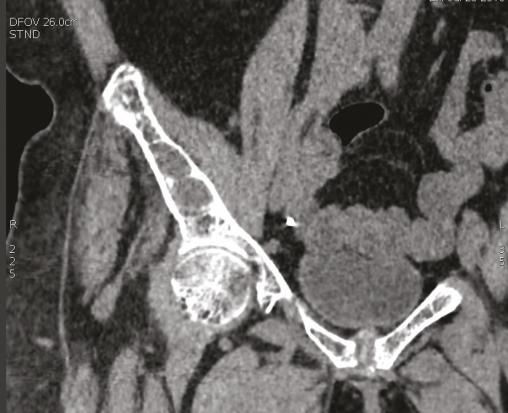

Cette patiente congolaise de 61 ans consultait pour des douleurs lombaires mécaniques anciennes très invalidantes. Les radiographies montraient une déminéralisation osseuse diffuse. La tomodensitométrie du bassin montrait une ostéolyse très particulière des deux sacro-iliaques (fig. 1) ainsi que des lésions fibrokystiques de l’aileron sacré droit (fig. 2). La calcémie était à 3,81 mmol/L, la parathormone était à 1 300 pg/mL (N : 6-50 pg/mL) confirmant le diagnostic d’hyperparathryoïdie primaire. La scintigraphie parathyroïdienne localisait une formation macronodulaire intensément fixante de 30 mm de grand axe au pôle inférieur du lobe thyroïdien droit (fig. 3). La patiente bénéficiait d’une parathyroïdectomie inférieure droite sous anesthésie locale, la calcémie se normalisait en 15 jours et les douleurs s’amélioraient en 3 mois.

Les lésions osseuses de l’hyperparathyroïdie primaire1 sont classiquement une ostéoporose et plus rarement une résorption sous-périostée des os longs ou de la symphyse pubienne, voire des sacro-iliaques (fig. 1). On peut observer des géodes ovalaires (fig. 2) disséminées (ostéite fibro- kystique de von Recklinghausen) avec des déformations osseuses. Après traitement, il est généralement observé une régression de l’ostéopénie et une persistance des lésions kystiques.